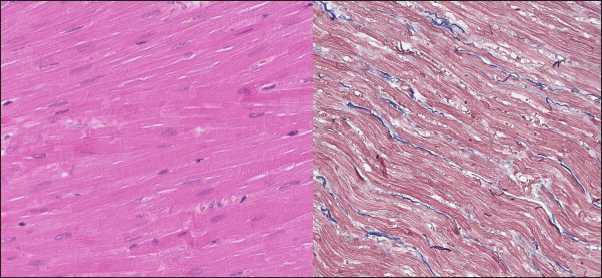

In the myocardium of cats with HCM we found a typical myocardial fibers disarray, with myocytes presented as thickened stripes branching in chaotic ways. Moreover, significant interstitial fibrosis was observed. Some myocytes were hypertrophied with multiple eccentrically located nuclei. Masson’s trichrome-stained samples showed myocardial fibrosis with interstitial and patchy patterns distributed around arteriolas and deep in the tissues (Fig. 5). Immunohistochemical staining with anti-Cx43 antibodies showed almost intact intercalated disks morphology in unaffected zones, but Cx43 expression began to fade near areas of developed fibrosis. In the transverse axis, we found increased expression of Cx43 on the lateral membrane (Fig. 6). In cardiomyocytes directly connected to the fibrotic tissue, cell-to-cell contacts were pale with almost no staining (Fig. 7).

Fig. 6. Immunohistochemistry. HCM group. Left—Transverse section, Cx43 proteins accumulated in the outer membrane periphery of the cardiomyocytes. Stained with Cx43 antibodies. Right—Longitudinal section, Cx43 proteins found in zones of cell-to-cell contact, but reduced in fibrotic and para-fibrotic zones. Stained with Cx43 antibodies.